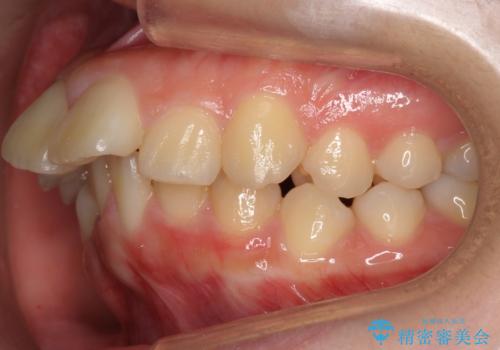

20代女性 出っ歯 口元を引っ込めたい

- 治療計画

- 出っ歯と前歯を気にして来院。

口元を下げたいとのことで、歯を抜いてワイヤー矯正を行いました。

上下左右の小臼歯を抜歯しています。